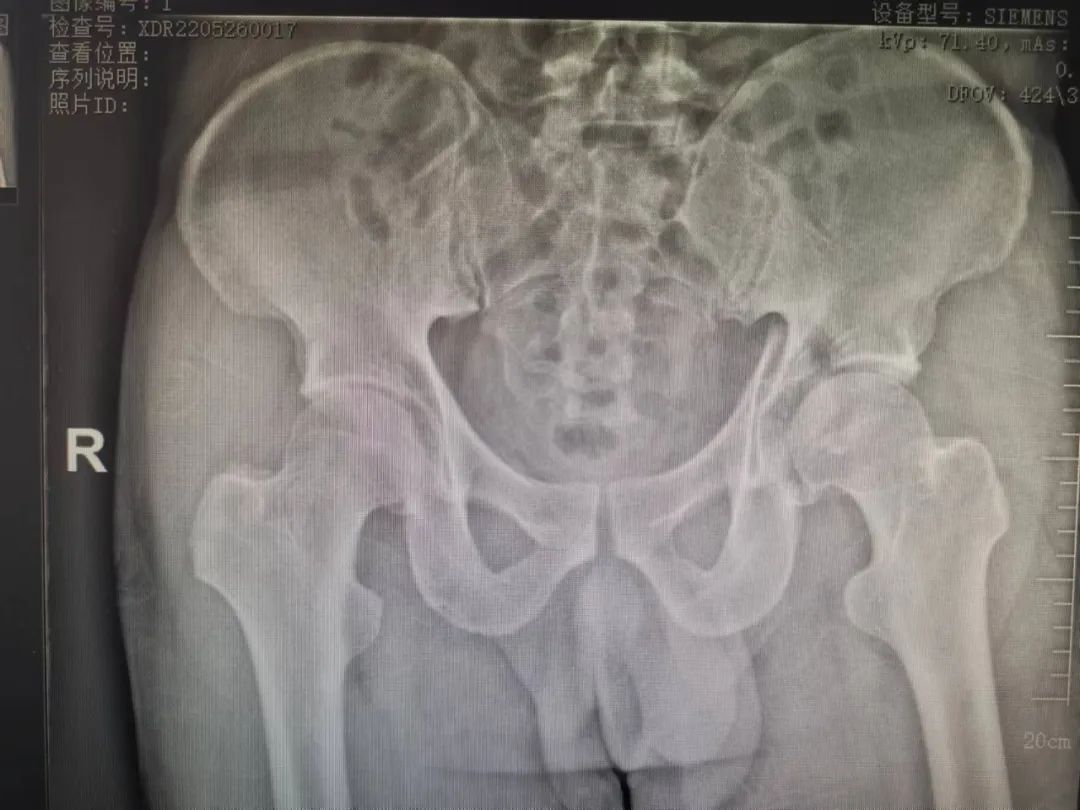

目前,复杂髋臼骨折的治疗仍然是骨科医生面临的最具挑战性的任务之一,随着创伤骨科的迅速发展,人们对创伤控制,加速康复理念的认知不断加深。近日,我院骨一科收治一名因高能量伤致左侧髋臼骨折,左侧胫骨平台骨折患者,其中髋臼骨折分型为:横行伴后壁骨折;胫骨平台骨折分型为Schatzker VI,二者均为该类骨折中最为严重类型,可见其损伤能量极高,如得不到合适的治疗,势必对预后造成致残后果。我院骨一科团队在刘利主任的主持下进行了该患者的术前讨论计划,为其实施了一期左胫骨平台骨折切开复位内固定手术。患者得到左下肢的初始固定后,准备开始着手行复杂髋臼骨折的手术。

张洪彬医生对患者骨盆三维CT进行了术前虚拟仿真,辅助术者规划骨折复位过程及通道螺钉的置入长度、角度及方向。在患者伤后2周内,由刘利主任主刀,采取单一Kocher-Langenbeck 入路手术入路,术中仔细对坐骨神经及旋股内侧动脉进行了保护,降低了远期发生神经损伤及股骨头缺血性坏死发生风险,完成复位后,应用两块重建钢板及一枚通道螺钉就完成了复杂骨折的固定。术后复查DR及CT骨折复位理想,内固定位置满意,没有发生螺钉进入关节腔的情况。患者得到了早期功能康复锻炼的有利条件。患者现已顺利出院。